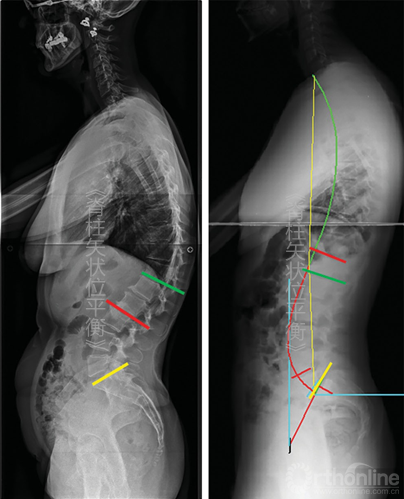

这种功能分段同样可在胸椎应用。脊柱前凸区域与后凸区域之间的关系是上凸区域与后凸区域之间的一种平等关系(图5-9)。

图5-9 根据Berthonnaud等的脊柱分段 CC.颈椎弯曲;SS.骶骨倾斜;TC.胸椎弯曲

在脊柱颈胸段也同样可以用弯曲顶点进行分段:胸椎后凸则定义为在两个拐点之间的弯曲,颈椎前凸定义为从C3至近端拐点之间的弯曲。因为成像技术(数字影响或EOS系统)已经能清晰的辨认T1椎体,T1椎体上终板的方向便有了更重要的意义。T1倾斜角即为T1上终板同水平线之间的夹角,其对理解颈椎弯曲方向有着重要的意义。

在功能性脊柱分段中,胸椎后凸形态与远端脊柱前凸形态相互影响。首先当胸椎后凸累及椎体长度增加时,远端脊柱前凸形态减小,反之亦然;其次角度方面,胸椎后凸的下弧角等于远端脊柱前凸的上弧角。

由此也引起了一个治疗方面问题,即在手术过程中,当远端腰椎前凸的长度和角度都因上弧角的延长被医源性增大时,胸椎后凸角度也会增加进而引起近端交界性后凸(proximal junctional kyphosis,PJK)。(未完待续)